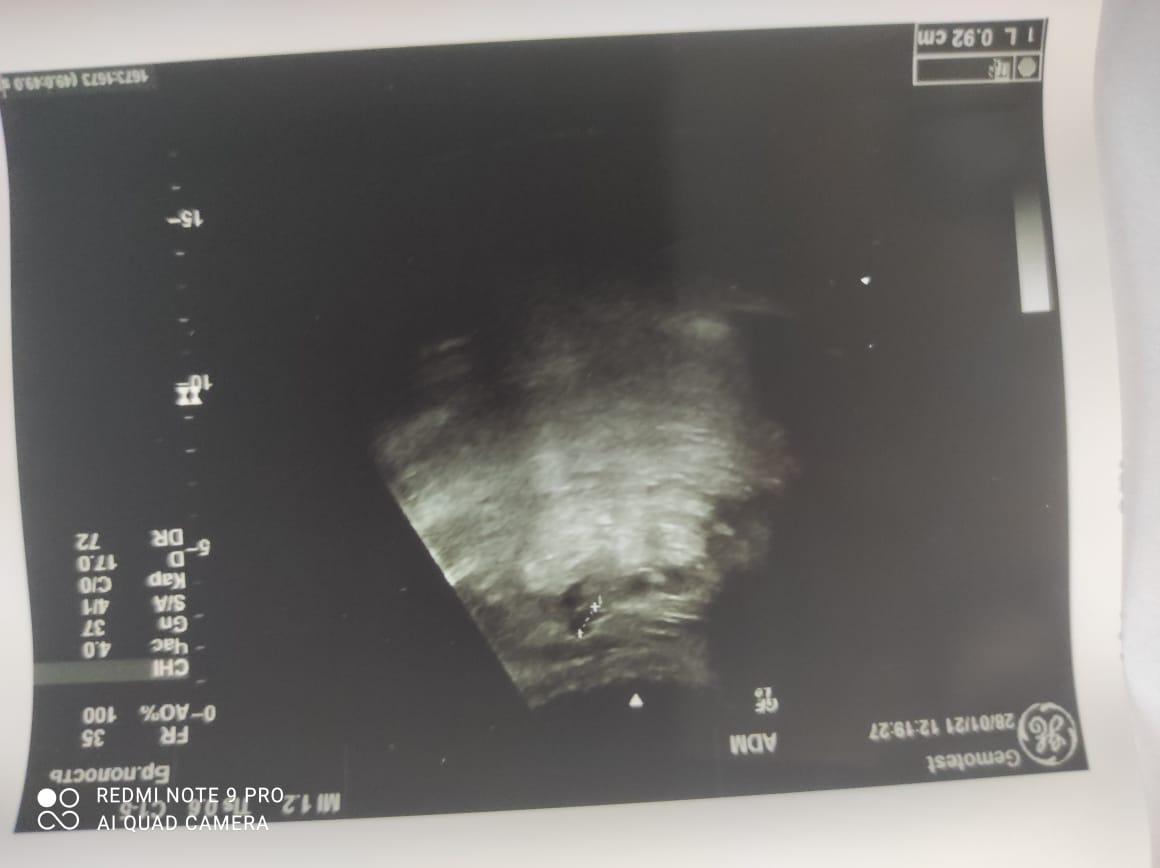

Здравствуйте! При наличии коралловидного камня правой почки(заключение УЗИ), можно предположить причиной боли нарушение уродинамики верхних мочевых путей), что, однако, не подтверждается результатами УЗИ почек( ЧЛС не расширена). Другая, наиболее вероятная возможная причина "боли в боку" - может быть патология опорнодвигательного аппарата. Необходимо проконсультироваться с неврологом и урологом очно, и согласовать возможность применения противовоспалительных, обезболивающих и спазмолитических препаратов - как первый шаг. В дальнейшем необходимо планировать возможное дальнейшее обследование и лечение. Удачи!